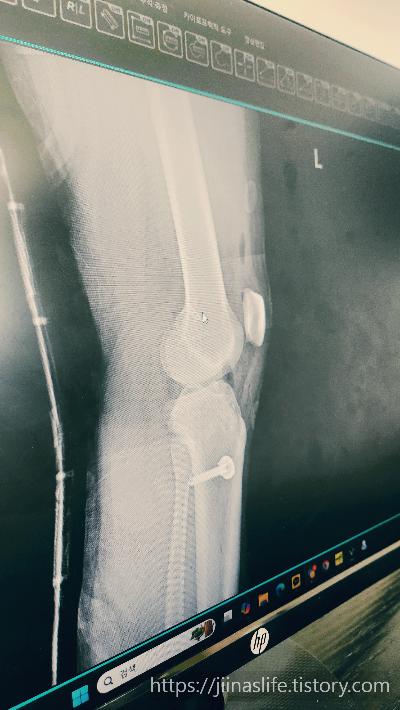

엑스레이로는 보이지 않았어요.

(엑스레이 상 무릎에 액체가 찼다고 주사로 빼봐야 한데요.)

수술방법은

뼈에 구멍을 뚫어서 타가건을 넣고

건을 고정하기 위해 위아래 뼈에 박는 것 입니다.

뼈를 뚫는 것에 겁나고

박는거에 놀라고

일 년 있다가 나사 하나는 빼야한다니 할 말을 잃습니다.

🔹 X-ray 검사: 골절 여부 확인

🔹 MRI 검사: 인대 손상 정도 및 연골, 반월상 연골 등 추가 손상 확인